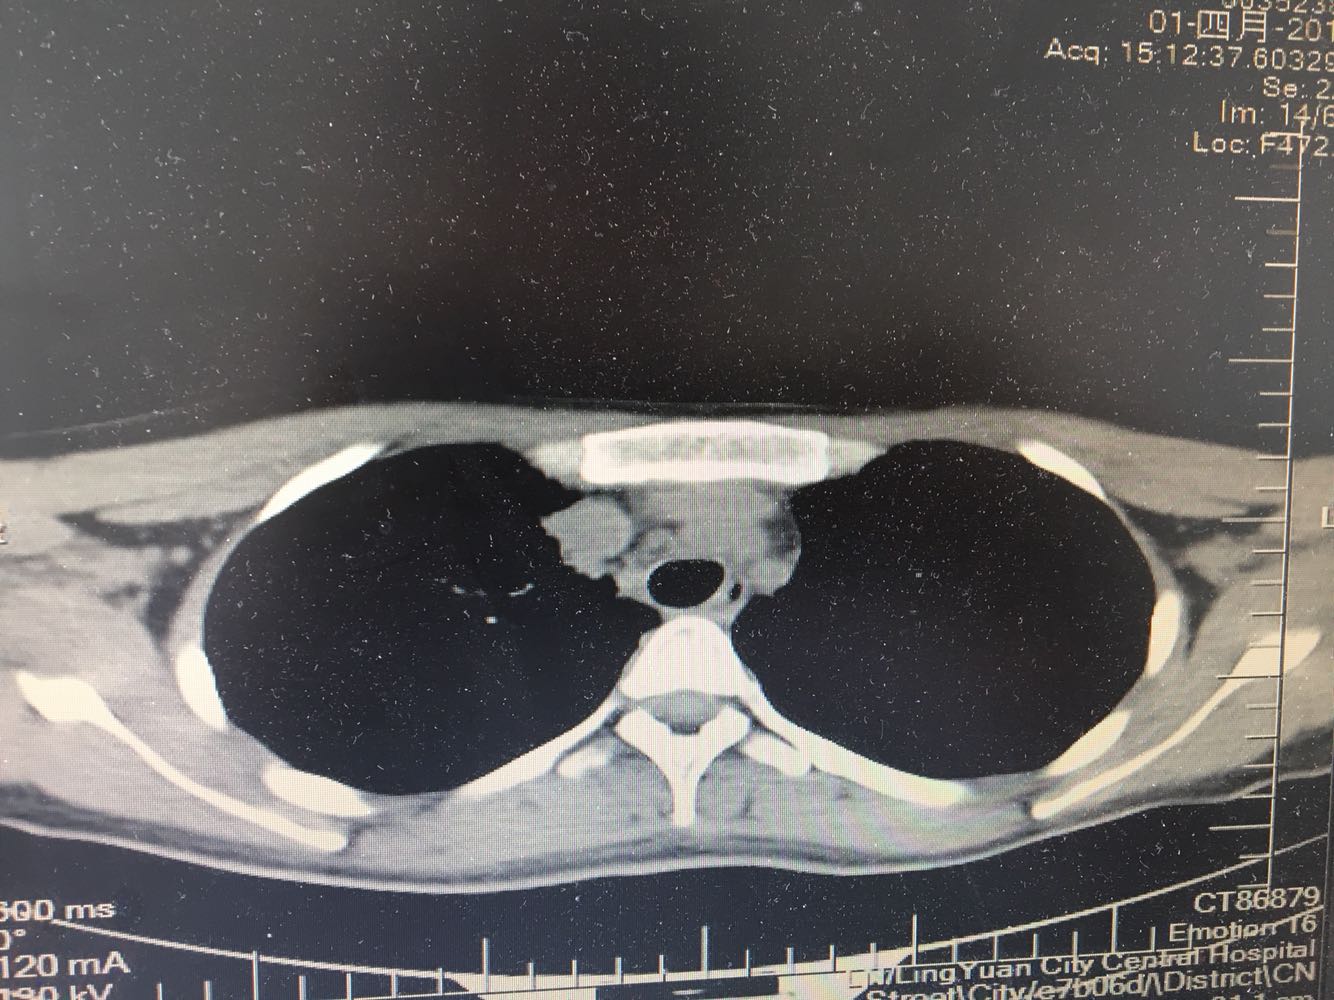

女,26岁,咳嗽1周,咳痰不畅,咽喉痒,口服阿莫西林无好转,昨日发热,体温38.5摄氏度,于门诊查肺CT后以肺炎收入院,病来无盗汗,无咳血,无消瘦及乏力,无头痛,无肢体酸痛,饮食睡眠可,二便正常

神清言明,咽部无充血,扁桃体不大,双肺呼吸音清,无罗音,服软无压痛。

支原体抗体1:160,结核抗体弱阳性。支原体肺炎个别可见上叶病变,该患无结核中毒症状,考虑支原体肺炎可能性大,但肺尖为结核好发部位,需要抗炎治疗后复查观察疗效。